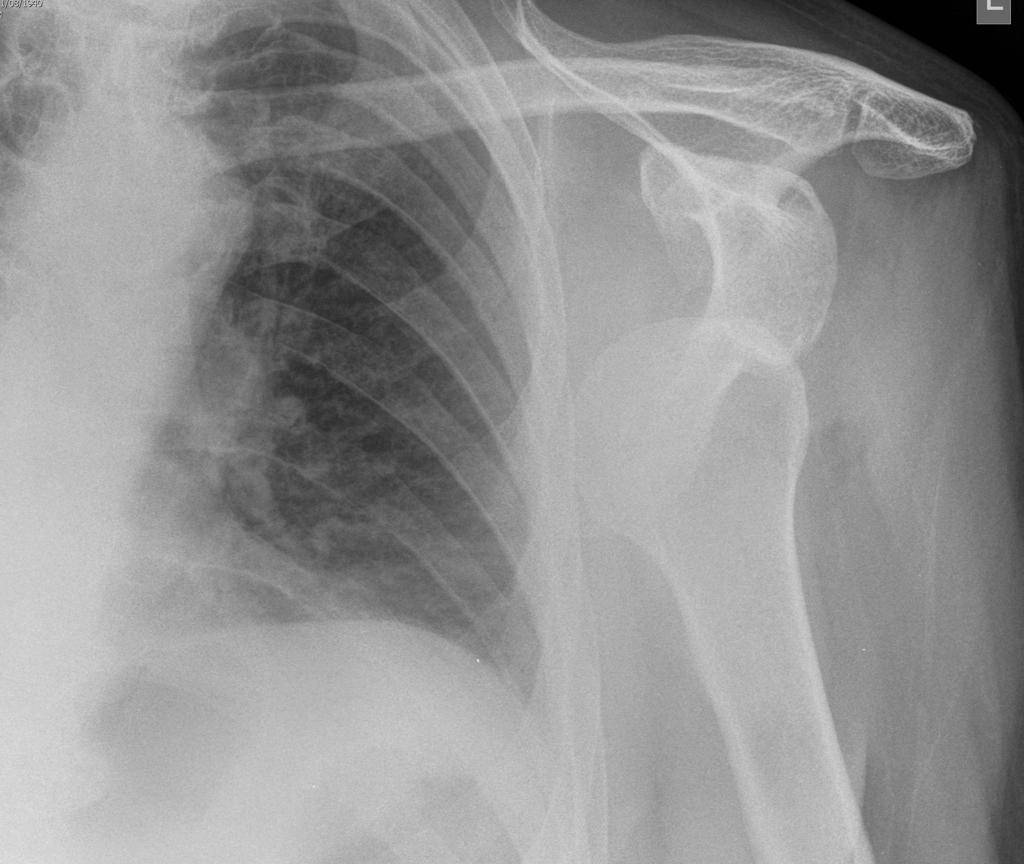

• Acromioclavicular joint separation

• Can obtain stress views (weight bearing) if initial radiographs normal but injury suspected

• Soft tissue swelling or stranding (may be only sign in Type 1)

• Widening of AC joint

• Widening of CC distance

• Superior displacement of distal clavicle (undersurface of clavicle should line up with undersurface of acromion)